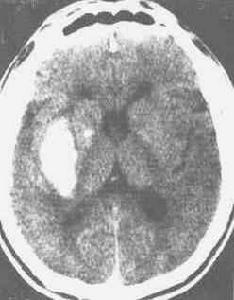

1.CT檢查可見對稱性基底核鈣化斑>800mm2,是該病重要的診斷標準,小腦齒狀核和大腦皮質也可有鈣化斑。